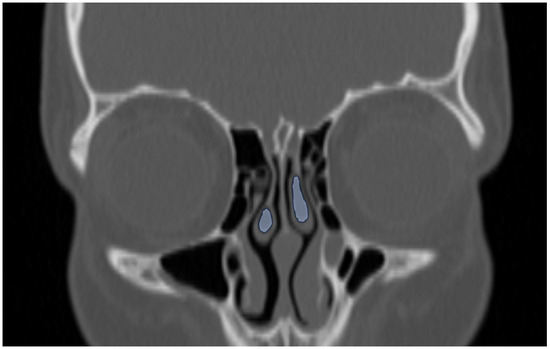

Background/Objectives: The aim of this study was to compare two methods for maxillary sinus volume measurement, assessing their accuracy. The analysis compared the maxillary sinus volume in patients with unilateral cleft lip and palate (UCLP) and in a non-cleft group, using a manual method and a three-dimensional (3D) semi-automated segmentation method. Methods: The research was conducted according to the STROBE guidelines. Sixty patients were included in this study: thirty patients with UCLP were in the research group, and the control group consisted of 30 patients with no craniofacial deformities. Cone-beam computed tomography (CBCT) was analyzed. The manual maxillary sinus volume was calculated based on its approximation to two geometric shapes based on mathematical formulas using linear measurements that were performed on all sinus CBCT scans in the maximum diameter in three planes. The semi-automatic segmentation method using ITK-SNAP 3D-imaging software version 4.2.2 was used to automatically calculate the maxillary sinus volume of the sinuses. The manually calculated volume was compared with the automatically calculated one, and statistical analysis was performed. Results: The cleft group presented lower values in both the automatic and manually calculated volumes for both the right (automatic: p = 0.49; manual p = 0.009) and left (automatic: p = 0.46; manual p = 0.11) maxillary sinuses than the non-cleft group. The cleft group presented statistically significant higher discrepancies in values between the manual and semi-automatic method than the control group (RMSV p = 0.0011; LMSV p = 0.033; TMSV p = 0.003). Conclusions: The manual method may not reveal the exact anatomical topography of the maxillary sinuses. In UCLP patients, the maxillary sinus anatomy may be more complex. Therefore, a semi-automated method may be more advisable to preserve the accuracy of the measurements. Full article

Show Figures

Figure 1